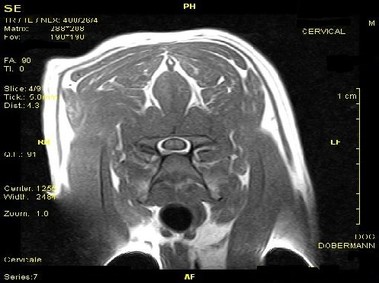

В настоящее время МРТ является наиболее предпочтительным методом визуализации любых мягких тканей, особенно для визуализации травм и патологий центральной нервной системы и суставов. Особенности Vet-MR позволяют использовать данный метод визуализации также в сфере ветеринарии.

Vet-MR специально разработана для визуализации небольших животных и является результатом внимания к деталям при разработке магнита, катушки и электронных компонентов, обеспечивая высокое качество экономически эффективной и простой в использовании МРТ в сфере ветеринарии.